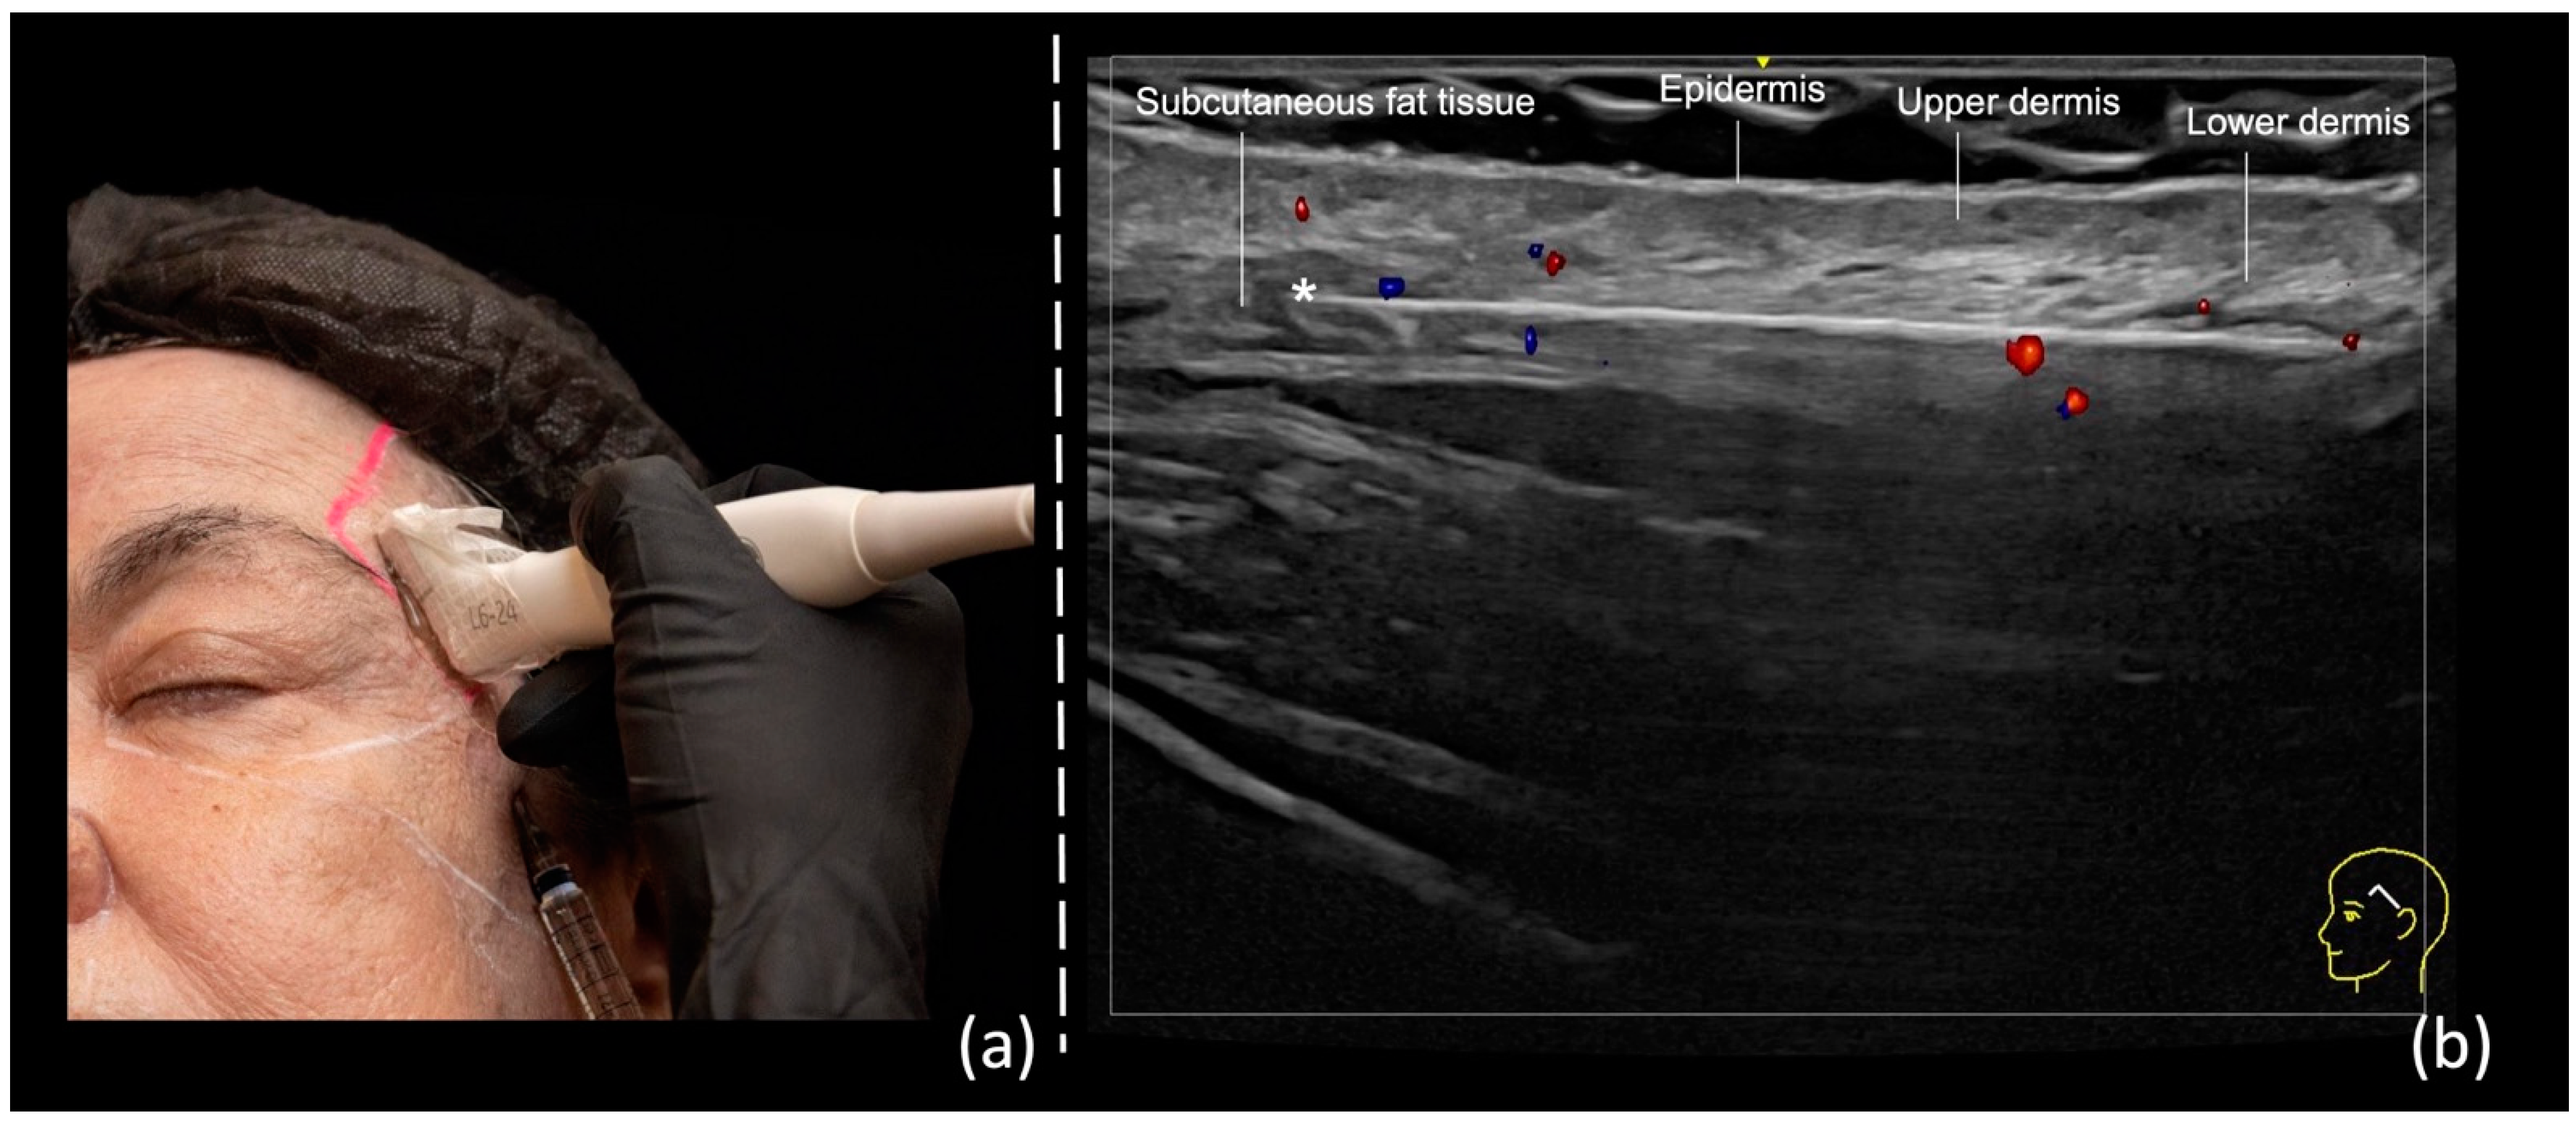

- Technique 1: Subdermal filler placement

| Temporal Region Technique 1: Subdermal filler placement | No | Yes | Subcutaneous fat tissue | Superficial temporal artery and vein |